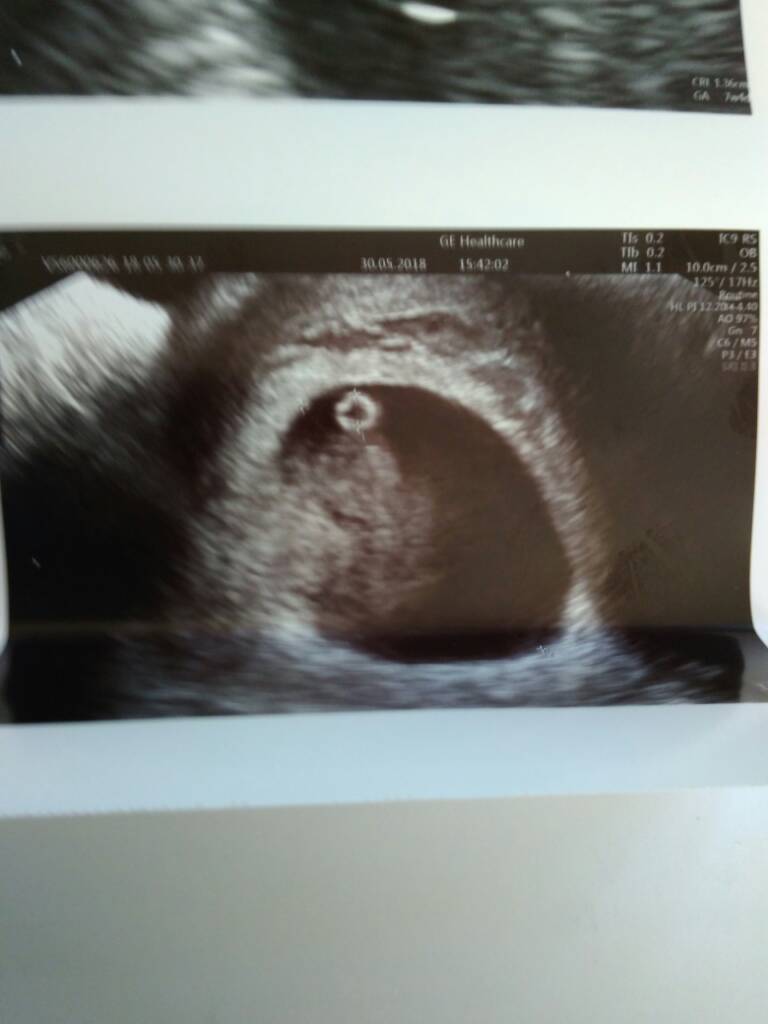

Hej dziewczyny,chciałam się pochwalić swoją dzidzia [emoji4] Po różnych zawirowaniach - plamienie 2 tygodnie temu , brak zarodka w 6 tc1d..po ostatnim Poronieniu nastawiałam się na różne scenariusze. Zdjęcie z dziś 7t6d , dzidzia ma idealne wymiary z USG i pokrywa się co do dnia z terminem OM. Serducho pięknie bije [emoji7] Jestem taka szczęśliwa. Ja też mam bardzo dobre wyniki badań i czuję się świetnie. Także wszystko jak powinno być. Teraz byle do końca trymestru..

IMG_20180530_172749.jpg